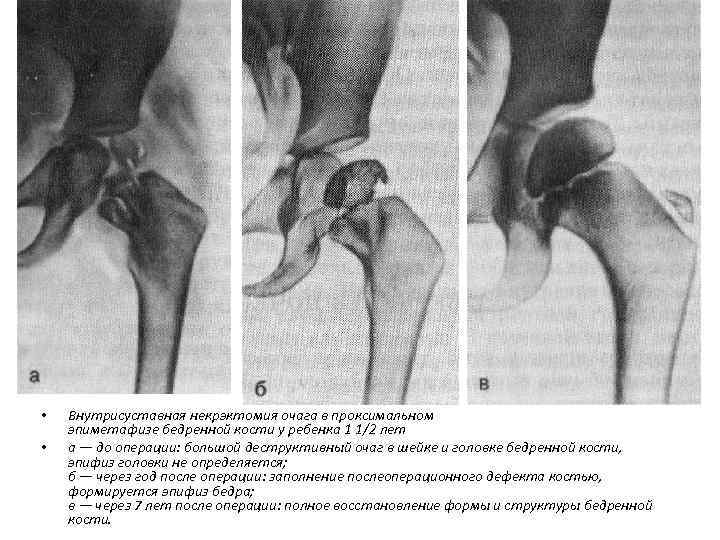

• • Внутрисуставная некрэктомия очага в проксимальном эпиметафизе бедренной кости у ребенка 1 1/2 лет а — до операции: большой деструктивный очаг в шейке и головке бедренной кости, эпифиз головки не определяется; б — через год после операции: заполнение послеоперационного дефекта костью, формируется эпифиз бедра; в — через 7 лет после операции: полное восстановление формы и структуры бедренной кости.

• • Внутрисуставная некрэктомия очага в проксимальном эпиметафизе бедренной кости у ребенка 1 1/2 лет а — до операции: большой деструктивный очаг в шейке и головке бедренной кости, эпифиз головки не определяется; б — через год после операции: заполнение послеоперационного дефекта костью, формируется эпифиз бедра; в — через 7 лет после операции: полное восстановление формы и структуры бедренной кости.